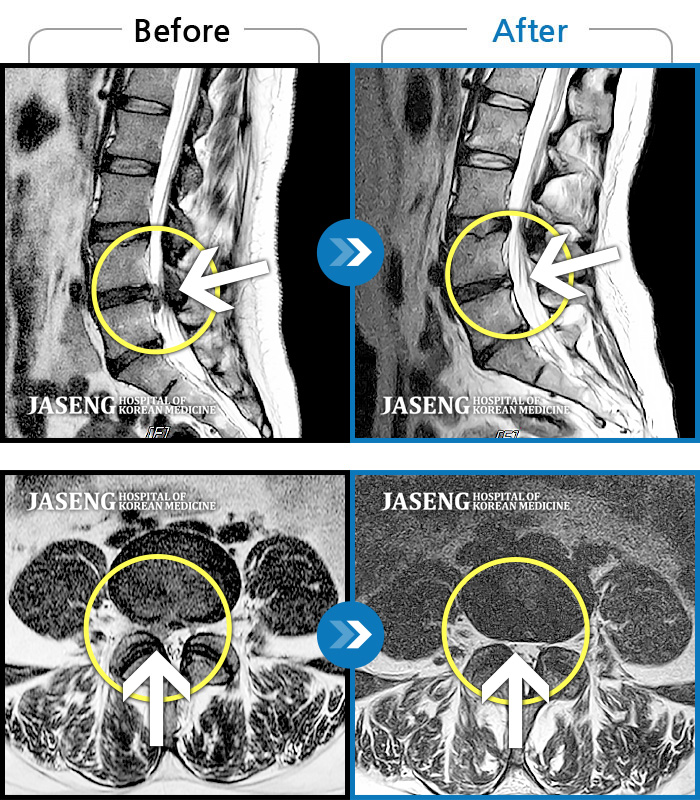

MRI 결과는 추간판협착증 2군데와 추간판탈출되어 터져서 디스크가 좌측으로 흘러내려 좌측 신경을 넓게 누르고 있는 곳이 1군데로 예상보다 심각한 상태였더군요.